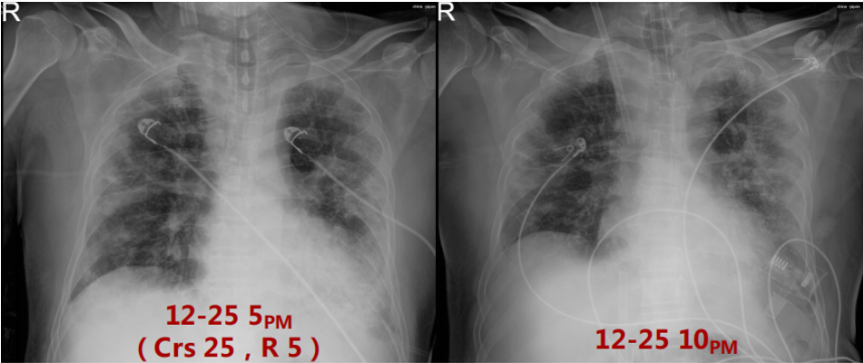

入科时,患者呼吸支持方式为HFNC,患者PFR<100 mmHg,故于当天下午行气管插管。呼吸机IPPV PC 18 cmH2O,PEEP 14 cmH2O,f 26次/min,监测分钟通气量(MV)7 L/min。粗测床旁呼吸力学指标,顺应性(Crs)25 ml/cmH2O,气道阻力(R)为5 cmH2O/(L·s)。插管后约半小时,患者出现严重的呼吸性酸中毒,调整呼吸机参数:PC 20 cmH2O,PEEP 12 cmH2O,f 32次/min,监测MV 12 L/min。复查血气分析PaCO2明显下降,但氧合指数持续小于80 mmHg,遂于12月25日晚行VV-ECMO。ECMO第1天炎症、免疫、感染指标(12月26日)Fet 790 ng/ml,CRP>200 mg/dl,IL-6 14.88 pg/ml;

注:VV-ECMO参数:2700~3045 r/min,BF 3.4~3.9 L/min,GF 3 L/min,FiO2 1.0影像:下图分别是患者起病14、21及25天的胸部CT对比,在抗炎之后,患者肺部实变部分有明显吸收,且范围缩小。患者影像学变化过程:单纯磨玻璃影→实变伴磨玻璃影→实变、磨玻璃影伴牵拉性支气管扩张。综合上述,抗炎治疗后患者炎症指标下降、氧合改善、影像学吸收,综合判断抗炎治疗有效。患者在插管后出现了严重的酸中毒,在增加分钟通气量后,仍难以改善高碳酸血症和低氧,故选择ECMO支持。插管后3天,为了加强气道管理予气管切开。在ECMO支持7天后,复查胸部CT发现少量纵隔气肿,故于当天下调PEEP至6 cmH2O。追溯患者发生气压伤的原因,可能与过高的呼吸驱动有关,上调瑞芬太尼和丙泊酚的泵入速度,加深镇痛镇静。2023年1月1日患者PaO2较前稍有下降,查体双肺湿啰音,无皮下气肿及气胸表现,所以再次上调PEEP至8 cmH2O。经过上述处理,患者呼吸频率仍在25次/min左右,潮气量约为500 ml。1月3日患者出现寒战,ECMO抖管,再次复查胸部CT发现纵隔气肿较前加重,下调PEEP至4 cmH2O。在瑞芬太尼镇痛基础上应用丙泊酚+咪达唑仑双联镇静,患者呼吸频率下降,维持在20次/min左右,潮气量降至400 ml。